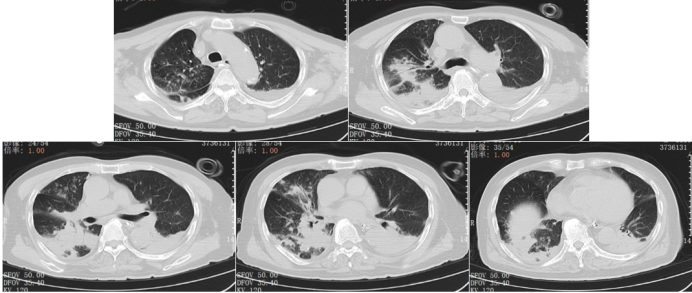

6. 影像学检查(2025-01-05,急诊)

肺部CT(图1): 肺气肿; 双肺新增多发感染、双肺间质性病变; 左上肺实性小结节(较前增大, 考虑炎性灶);右下肺钙化灶、气管旁憩室。

1  患者入院胸部CT(2025-01-05)